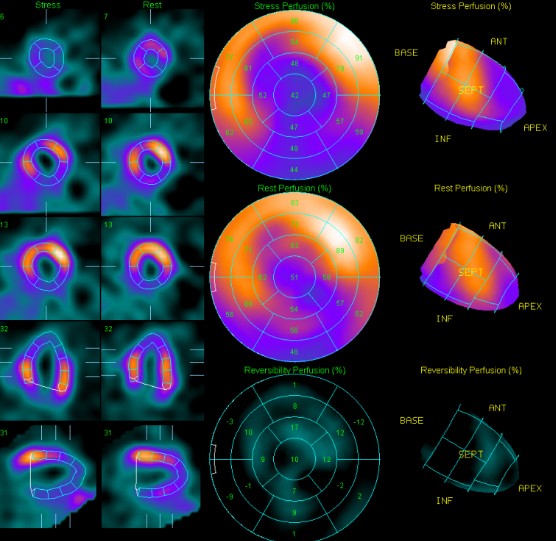

An electrocardiogram demonstrated sinus rhythm with poor R progression. Echocardiogram showed LA, LV dilatation , Impaired LV systolic function (A4C 31% ), impaired LV diastolic function.Previous Thallium-201 myocardial perfusion scan showed fixed perfusion defects in the apical, inferolateral, proximal inferior, and inferoseptal walls of the left ventricle, suggestive of prior myocardial infarction with mixed viable and nonviable myocardium.